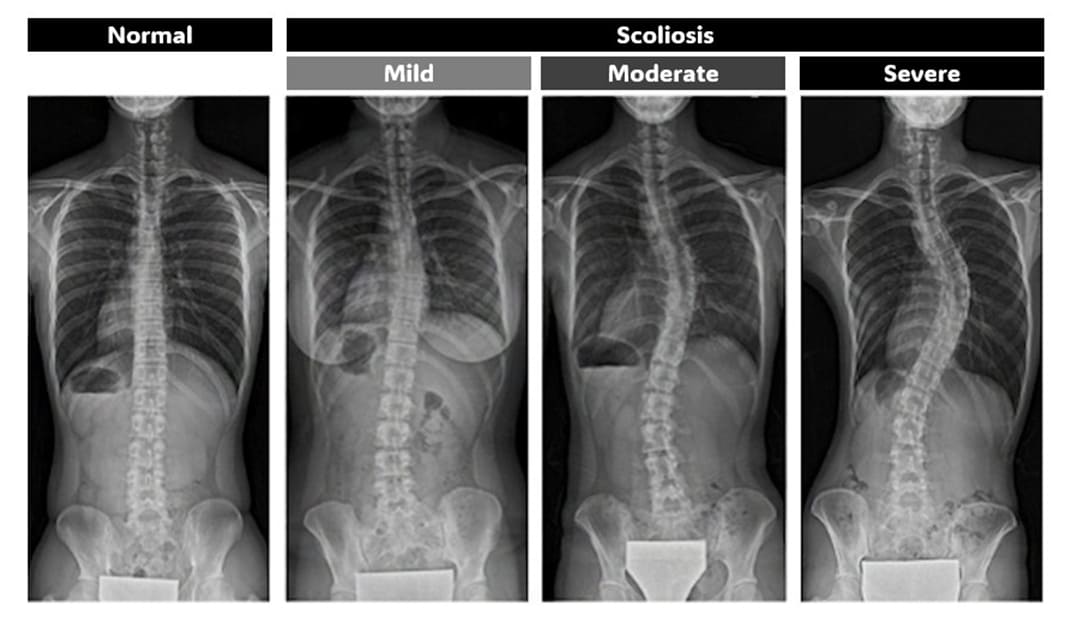

Scoliosis is a three-dimensional curvature of the spine. It affects an estimated 2-3% of children and often progressing rapidly during adolescence. If left undetected, it can lead to chronic pain and long-term respiratory complications, making early detection critical. However, traditional screening methods, such as visual and physical examinations, rely heavily on practitioners’ experience, often missing early-stage cases, while X-ray carry radiation risks that limit how often they can be used. SMILE CURVE addresses these challenges with a radiation-free 3D scanning system designed for use in schools and clinics. Our system allows practitioners to regularly measure and monitor children’s spinal changes for early scoliosis detection. Early detection enables timely, non-invasive treatments such as bracing before surgery becomes necessary. We are dedicated to early scoliosis detection and help protect each child’s long-term health and well-being.

X-ray image of the spine and scoliosis